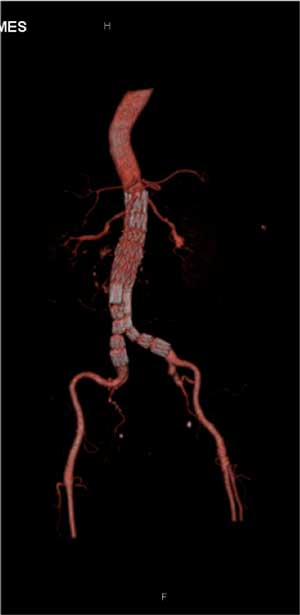

A seguir segue o exemplo de um paciente tratando por via endovascular de aneurisma de aorta abdominal, e suas tomografia pré-operatória e no controle de 30 dias.

Uma das maiores dificuldades técnicas para o tratamento endovascular é o envolvimento de artérias renais no aneurisma, quando a origem destas artérias ocorre dentro da aorta dilatada.

Assim, para que ocorra uma correta fixação da endoprótese na parede da aorta, é necessário liberá-la acima da origem das artérias renais. No caso a seguir, Para evitar a oclusão das artérias renais confeccionamos orifícios laterais na endoprótese (fenestração) para manter o fluxo das artérias renais. Para tanto, introduzimos um stent em cada artéria renal.